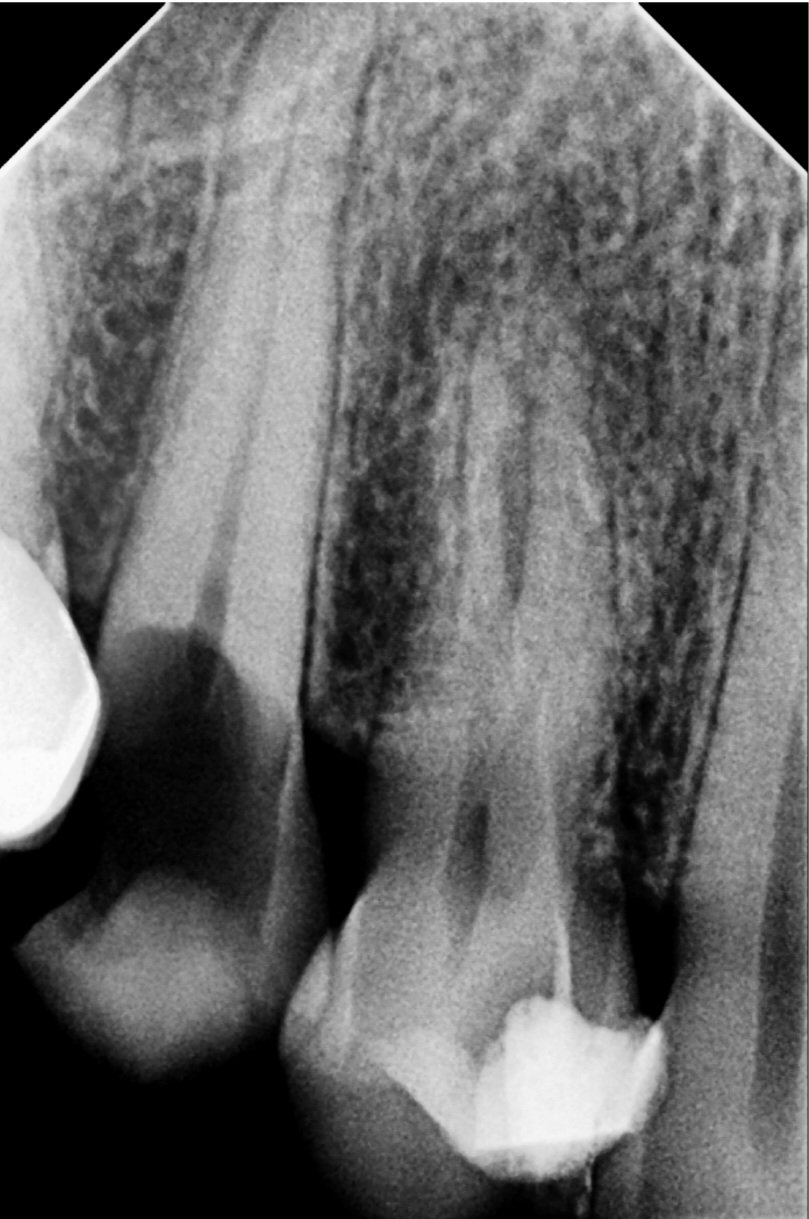

What Happens If You Delay Treatment?

Avoiding or delaying root canal treatment can lead to:

• Spread of infection to other teeth or jawbone

• Formation of abscesses or cysts

• Tooth loss

• Complications that require more expensive procedures